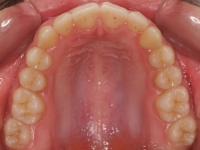

La paciente O.O. acude a nuestra consulta por:

– Canino 13 e incisivo lateral 42 en posición ectópica.

– Canino 23 incluido.

Con lo que decide realizarse un tratamiento de ortodoncia de duración de 24 meses con brackets damon Q.

CASO COMPLETO: